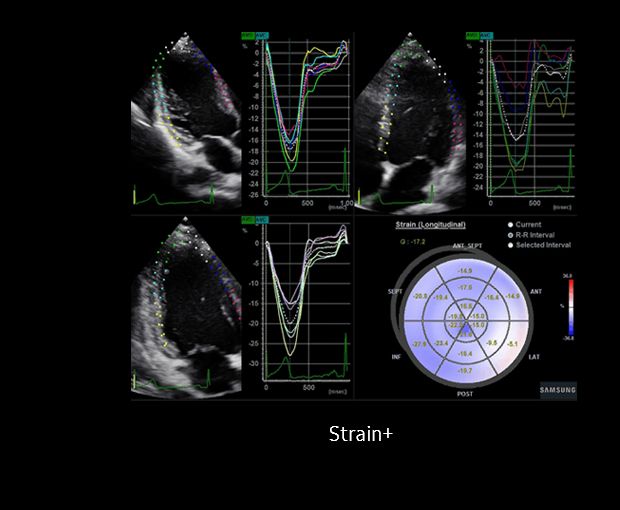

льный стрейн

Продольный стрейн 105 фото